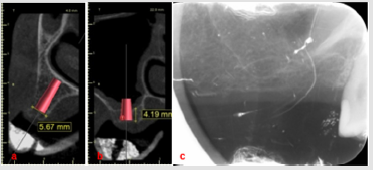

A 40-year-old female patient was referred to the Prosthodontics department in our School of Dentistry in January 2018. The patient’s informed consent was obtained to include her photographs and radiographs in our study. Intra-oral examination of the maxillary arch (Figure 1) revealed multiple carious lesions which were restored with composite resin. Remaining roots of maxillary left premolars and first molar as well as non-restorable maxillary left second molar, due to extensive subgingival caries, were extracted. Implants insertion was delayed for 6 months after extraction to allow for complete remodeling of the extraction sockets. CBCT requested two weeks prior to implants’ placement showed slightly deficient bone bucco-lingually in the maxillary left first premolar region (Figure 2A). Furthermore, diminished bone height (4.19 mm) was evident in the left second molar region (Figure 2B). Hence, densah bur was used for ridge expansion and crestal sinus lift in the left first premolar and second molar respectively.

Figure 2: Radiographs requested 6 months post-extraction. a. CBCT showing slightly deficient bone width for implant in the first premolar region, b. CBCT showing maxillary sinus pneumatization and reduced bone height for implant in the second molar region, c. Peri-apical radiograph showing severe sinus pneumatization.

Peri-apical x-rays were taken prior to implant surgery for comparative purposes (Figure 2C). In the first premolar region, drilling using Densah burs (VS8) proceeded under counterclockwise pumping motion (Figure 3A). During insertion of the final drill (3.5×11.5 mm), fenestration of the buccal wall of the osteotomy occurred. Implant (4×11.5 mm) (Neobiotech, Korea) was inserted and the dehiscence was managed by grafting with DM Bone (Neobiotech, Korea) and T-Gen membrane (SK bioland Co., Korea) (Figure 3B). In the second molar region, pilot drill was inserted 1 mm short of the sinus membrane. Particulate DM Bone was packed into the prepared osteotomy. Sequential drilling then proceeded employing 200 rpm speed without irrigation, so that the densah bur can push the grafts coronally (Figure 4A & 4B). The compacted grafts lifted the sinus membrane gradually until reaching the desired height (8 mm), followed by implant (4×7.3 mm) insertion (Figure 4C). Implant stability quotient (ISQ) of both implants was measured on the day of surgery, 3 and 6 months postoperatively (Ostell, Sweden) (Table 1). After 6 months, the implants were restored with porcelain fused to metal screw-retained bridge using CCM UCLA abutments (Neobiotech, Korea) (Figure 5A & 5B). The patient was followed-up for a period of six months with no complications.